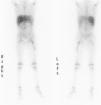

A continuación se presenta el caso de una niña de 5 años que acudió a Urgencias por fiebre e impotencia funcional en miembro inferior izquierdo de 5 días de evolución. Estaba en tratamiento con cefixima por faringoamigdalitis aguda. En la exploración presentaba posición antiálgica, con cadera izquierda en flexión y rotación externa, muslo edematoso, doloroso a la presión, e imposibilidad de movilización de la cadera. El resto de la exploración fue normal. El hemograma, la bioquímica y la coagulación resultaron normales. La proteína C reactiva (PCR) fue de 159,6mg/l. En la ecografía de cadera y muslo se observó aumento de grosor y ecogénesis del vasto lateral del cuádriceps; no se observó derrame articular. Al ingreso, se realizó gammagrafía ósea con Deoxipiridinolina–tecnecio 99 metaestable (DPD–Tc99m) que dio como resultado reacción inflamatoria en el muslo izquierdo e hipercaptación en el tercio proximal del fémur. La niña ingresó con diagnóstico inicial de osteomielitis. Se pautó tratamiento antibiótico intravenoso con cloxacilina y cefotaxima, y tratamiento antiinflamatorio con ibuprofeno oral. Ante la posibilidad de piomiositis asociada a osteomielitis femoral, se realizó gammagrafía con galio (fig. 1) y se evidenciaron 2 focos de captación: uno en la cabeza y el cuello de fémur, y otro en el vasto lateral del cuádriceps. La ecografía de control al alta mostró lesión hipoecogénica en el vasto lateral compatible con absceso muscular. Se realizó una RM (fig. 2), en la que se observó afectación difusa de cabeza y cuello de fémur izquierdo, y otra lesión hiperintensa de 10 × 1cm en el vasto lateral. La niña evolucionó favorablemente con el tratamiento médico y no precisó abordaje quirúrgico. La fiebre se suspendió al cuarto día del ingreso, con mejoría progresiva de la movilidad activa y pasiva de la cadera, y desaparición de la tumefacción en el muslo. La deambulación al alta era normal. El hemocultivo fue estéril y no se realizó cultivo del músculo ni del hueso. El tratamiento antibiótico intravenoso se mantuvo hasta completar 21 días y al alta se pautó amoxicilina con ácido clavulánico por vía oral.

Para mejorar el pronóstico y evitar que la enfermedad alcance la tercera fase, es importante un diagnóstico precoz y un tratamiento adecuado. Las pruebas de imagen son fundamentales1,4; la más conveniente es la RM, que proporciona información acerca de la afectación local y del tamaño. La gammagrafía con galio es útil a la hora de encontrar otros focos, ya que la piomiositis puede ser multifocal hasta en un 40% de los casos3. Del 5 al 40% de las veces, el hemocultivo es positivo y la conveniencia del cultivo del exudado recogido por punción o drenaje alcanza porcentajes cercanos a la totalidad de los casos1. Otras pruebas útiles son la ecografía (que debe realizarse en primer lugar debido a su seguridad, accesibilidad y bajo coste), la radiografía y la gammagrafía con DPD-Tc99m para detectar una posible afectación ósea.